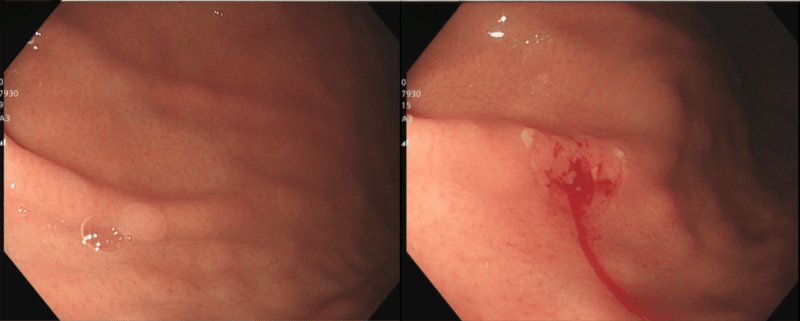

Hình ảnh khối u tại đại tràng có kích thước khoảng 1cm

Nội soi đại tràng cho thấy, cách ống hậu môn 6cm có khối đẩy lồi niêm mạc kích thước khoảng 1cm, màu vàng nhạt, niêm mạc phía trên giống niêm mạc xung quang, thăm thấy chắc, di động. Đây là hình ảnh nội soi gợi ý điển hình của u thần kinh nội tiết.

Hình ảnh khối u sau khi được cắt bỏ

Trên cơ sở đánh giá tổn thương, bác sĩ đã chỉ định cắt bỏ khối u dưới nội soi bằng kỹ thuật cắt niêm mạc qua nội soi (EMR) cải tiến và gửi mẫu làm giải phẫu bệnh. Kết quả là u thần kinh nội tiết, độ I, diện cắt không có u.

Với kết quả trên, bệnh nhân được chẩn đoán mắc u thần kinh nội tiết trực tràng độ I đã được cắt bỏ hoàn toàn và hẹn nội soi kiểm tra lại sau 3 tháng.